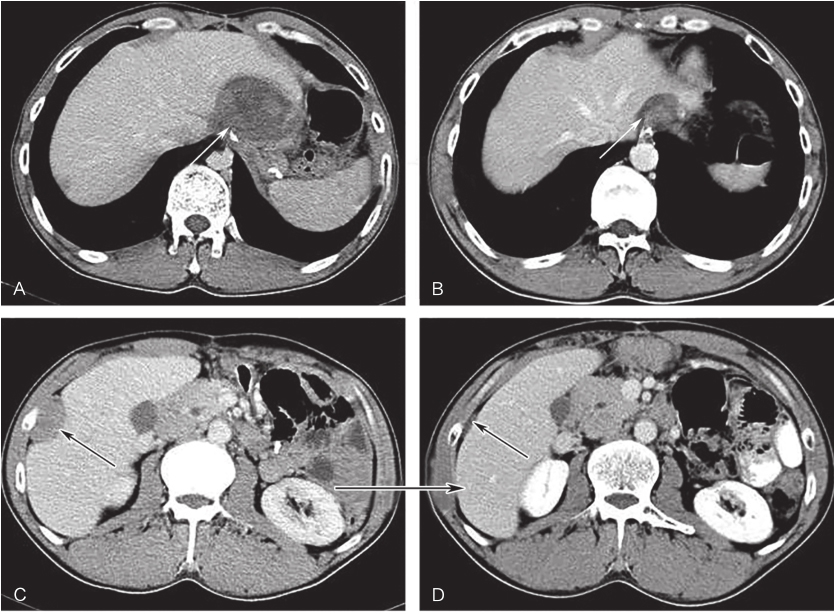

全腹部增强CT:左上腹软组织肿块,大小约16.4cm×12.3cm,考虑胃底大弯侧来源GIST伴左侧膈肌侵犯可能性大,需与淋巴瘤、神经鞘瘤、平滑肌瘤等其他胃黏膜下少见肿瘤鉴别(图1、图2)。

图1首诊全腹增强CT示胃底大弯侧来源GIST

图2首诊CT三维重建示左侧膈肌侵犯可能性大

于2012年10月13日开始口服伊马替尼400mg/d 治疗。治疗3个月后CT评估肿瘤大小为120mm×87mm,治疗6个月后CT评估肿瘤大小为92mm×65mm。治疗8个月后CT示:胃底大弯侧GIST,伊马替尼治疗后,肿瘤明显退缩,大小为89mm×63mm,病灶与左侧膈肌接触面缩小,分界较前清晰(图3)。此间规律口服伊马替尼,主要不良反应为1~2度食欲减退、乏力、手足综合征,未予特殊处理,自行缓解。

2016年1月4日,开始口服舒尼替尼37.5mg/d,连续用药。此间出现高血压、手足综合征、乏力等1~2度不良反应,未予特殊处理,自行缓解。每3个月复查全腹CT。口服舒尼替尼3个月、6个月、9个月后吻合口病灶大小分别为:51mm×49mm、35mm×26mm、31mm×15mm,肝被膜下病灶分别为:36mm×20mm、21mm×6mm、21mm×5mm,最佳疗效PR(图5)。

图3术前治疗8个月后全腹增强CT

图4伊马替尼辅助治疗30个月后全腹增强CT(冠状位)

白色箭头示吻合复发病灶,黑色箭头示肝包膜转移灶

图5舒尼替尼治疗9个月后增强CT表现

A、C.治疗前病灶;B、D.治疗9个月后病灶;白色箭头示吻合复发病灶,黑色箭头示肝包膜转移灶